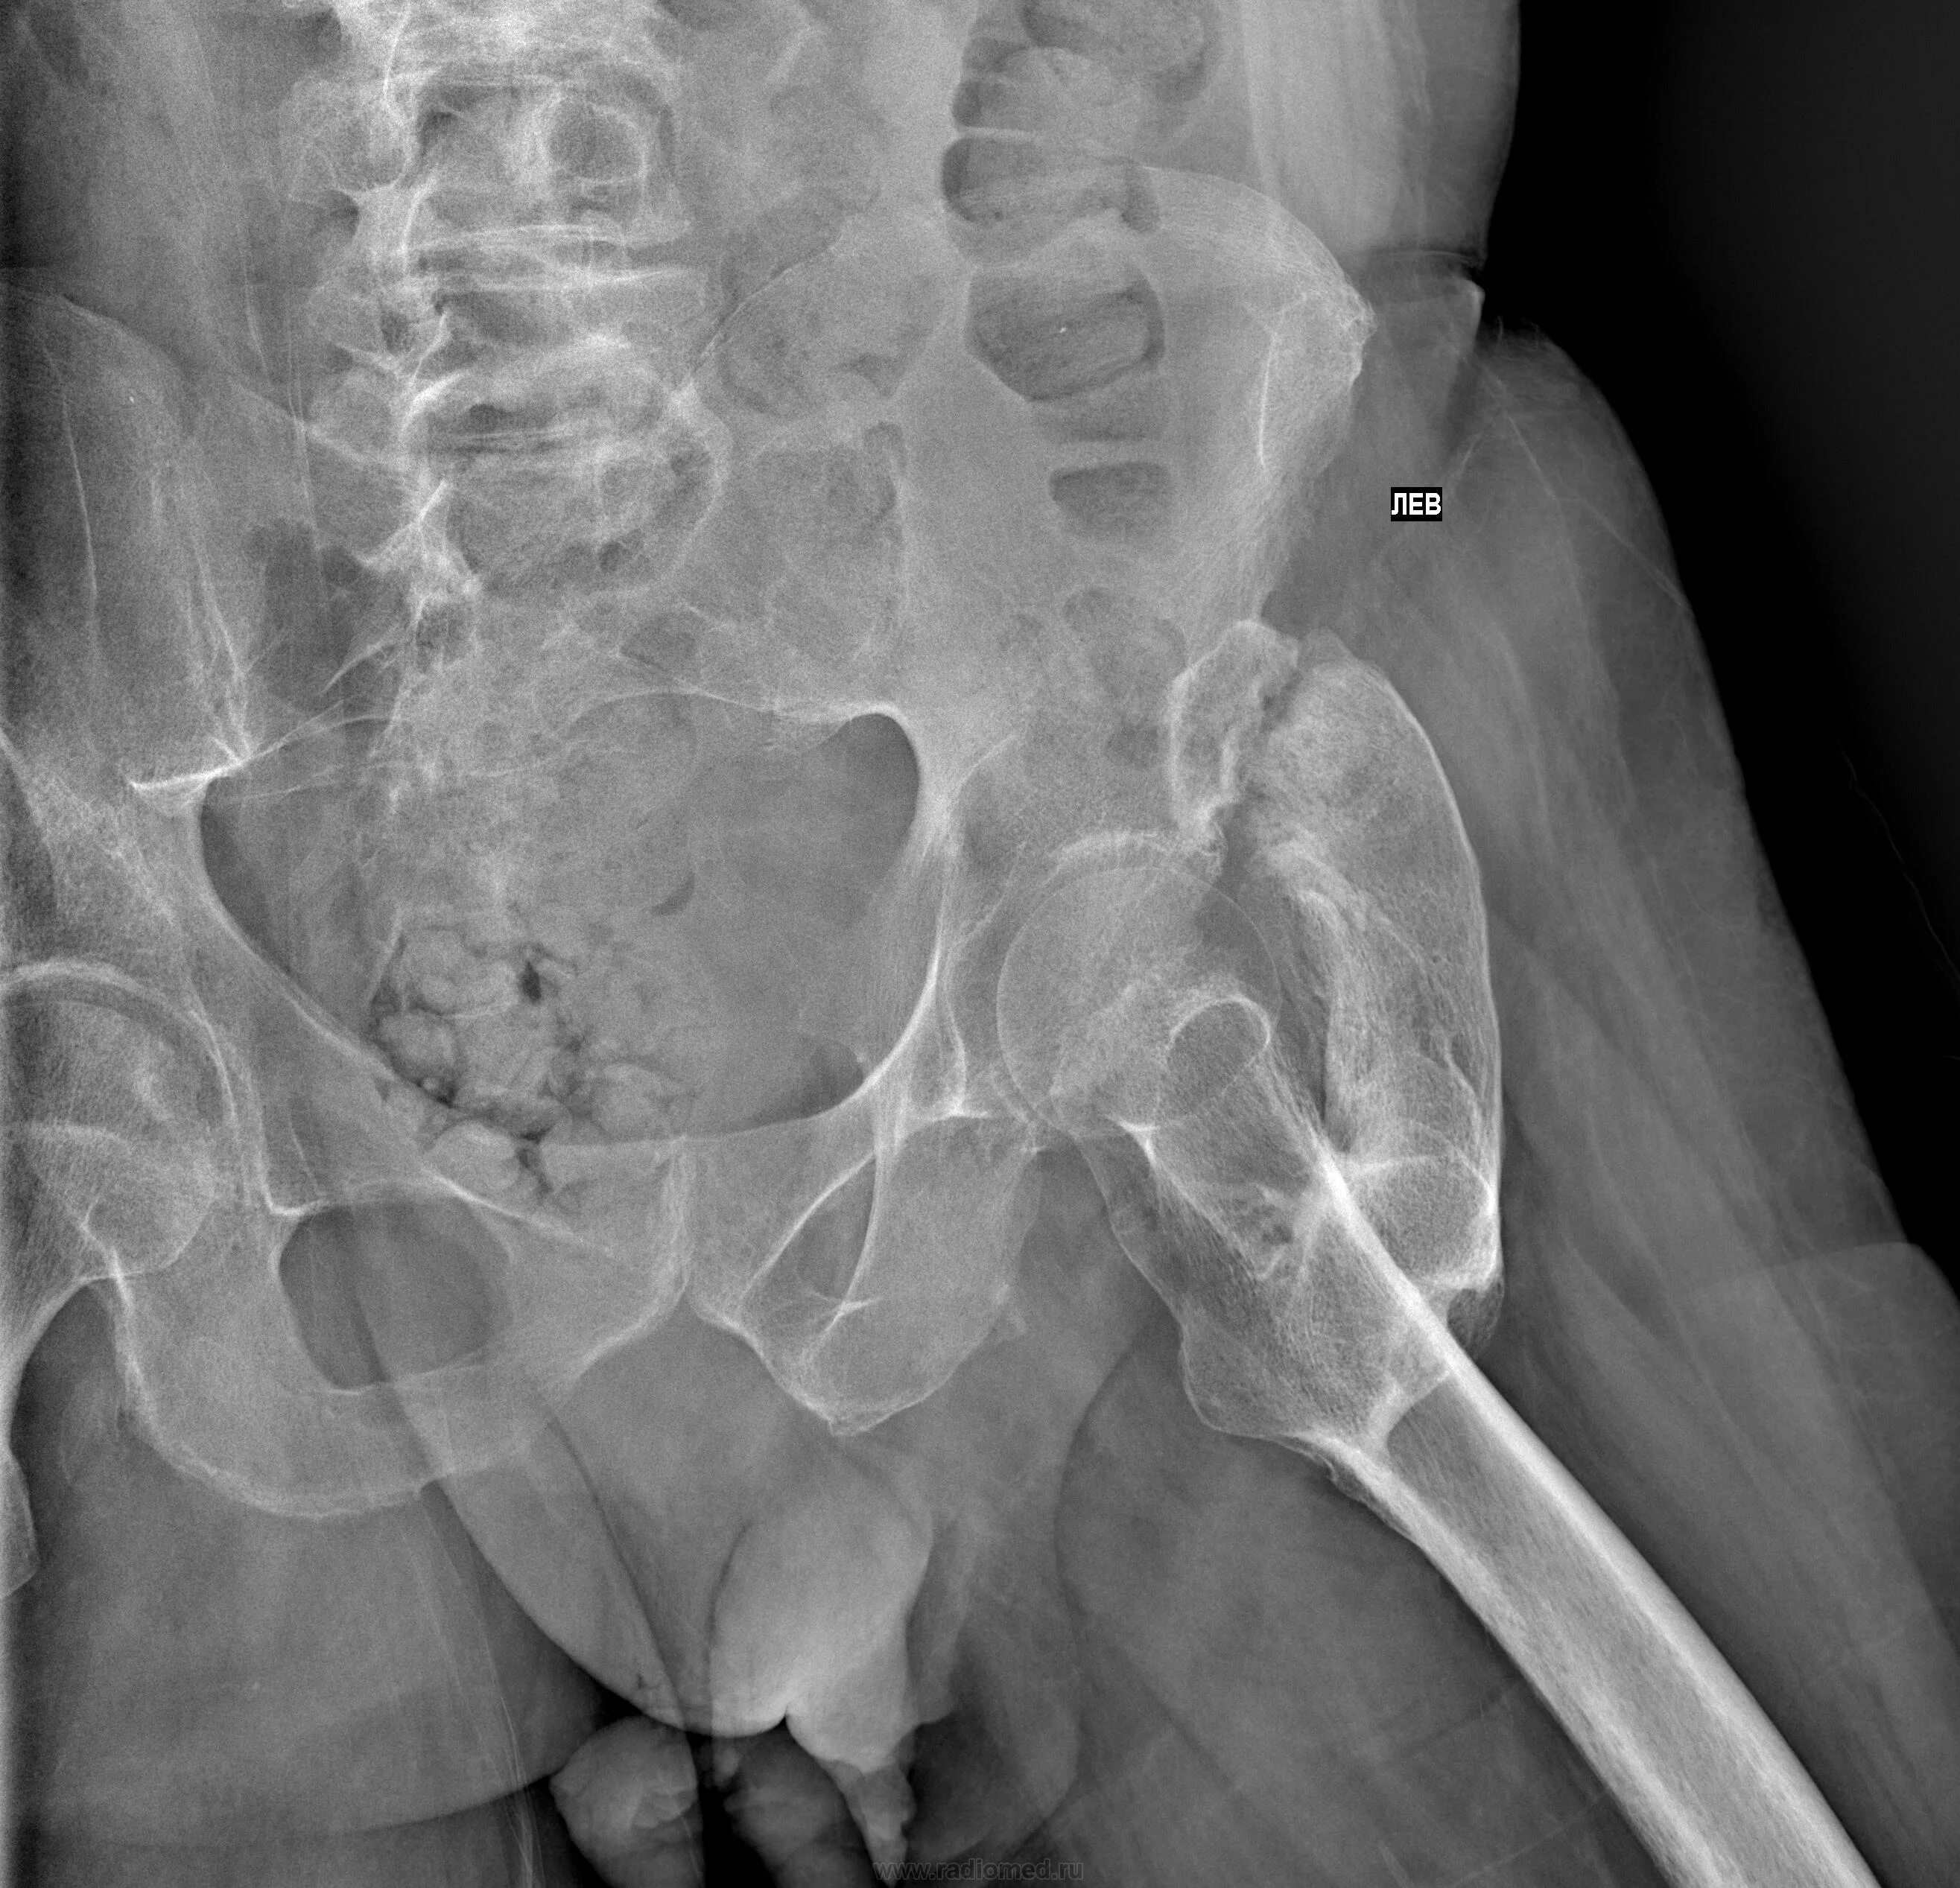

Оссифицированный миозит